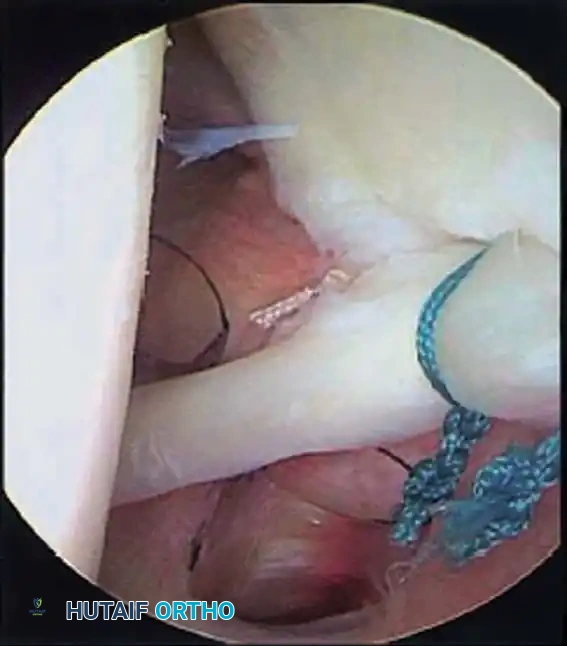

Once diagnostic evaluation is complete and hemostasis is secured, the therapeutic phase commences. Whether performing a SLAP repair, a Bankart stabilization, or a rotator cuff repair, the principles of tissue mobilization, anatomical footprint restoration, and secure biomechanical fixation remain paramount.

Modern arthroscopy relies heavily on suture anchors (biocomposite or all-suture constructs) and advanced arthroscopic knot-tying or knotless techniques. The ability to pass sutures through retracted, fibrotic tissue and secure them under appropriate tension without strangulating the microvascular supply is the hallmark of a master arthroscopist.